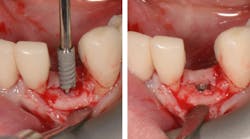

Placement of narrow implants. In a full-arch restoration in the presence of alveolae and thin ridges, narrow implants allow the placement of more biomaterial in the alveolae for ridge preservation. Bone grafting will be avoided in the presence of the ridges.